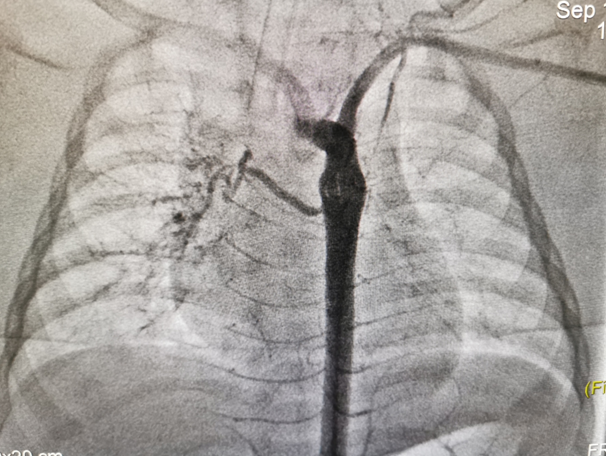

近日,青島婦兒醫(yī)院血管瘤&脈管畸形??瞥晒ν瓿梢焕夤軇?dòng)脈肺動(dòng)脈瘺介入栓塞手術(shù)。

入院完善檢查后,冉冉被確診為“支氣管動(dòng)脈肺動(dòng)脈瘺”。

這是一種少見的先天性血管畸形,只能通過介入或外科手術(shù)治療??紤]寶寶病情危重,血管瘤&脈管畸形??凭o急聯(lián)系心臟中心、心血管麻醉、導(dǎo)管室等團(tuán)隊(duì)進(jìn)行支氣管動(dòng)脈肺動(dòng)脈瘺介入栓塞手術(shù)。

術(shù)中在DSA引導(dǎo)下超選擇性推注聚乙烯醇(PVA)微球,僅用一個(gè)小針眼就順利栓塞了變異的血管,沒有任何金屬植入物便達(dá)成了封堵支氣管動(dòng)脈肺動(dòng)脈瘺的療效,既避免了外科手術(shù)創(chuàng)傷及手術(shù)切口瘢痕的形成,又避免了終身植入彈簧圈等金屬封堵物。術(shù)后當(dāng)天,冉冉就回到了媽媽身邊。目前,患兒已治愈出院。